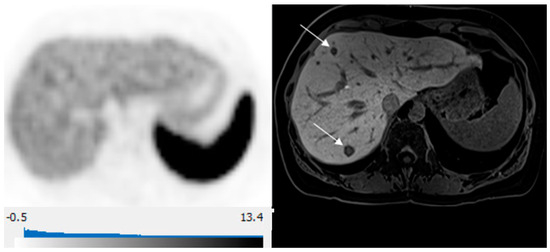

| T2 signal intensity | High | 46 (47) |

| Intermediate | 45 (46) | |

| Low | 7 (7) | |

| Restricted Diffusion | Yes | 85 (87) |

| Equivocal | 2 (2) | |

| No | 11 (11) | |

| Arterial Enhancement | Yes | 72 (73) |

| No | 26 (27) | |

| Wash Out | Yes | 75 (77) |

| No | 23 (23) | |

| Visible on HBP | Yes | 98 (100) |

| No | 0 |